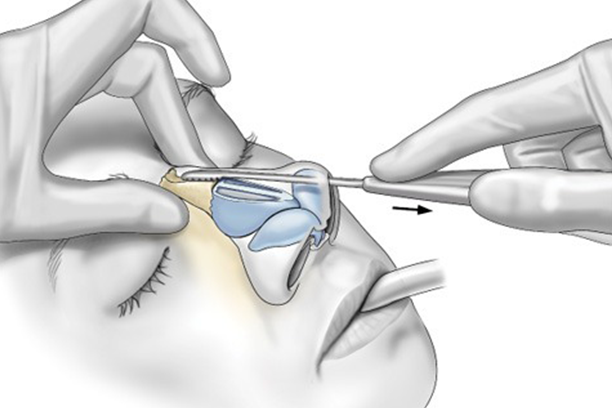

Balloon Sinuplasty

CSF Leak Repair

Sinus Surgery (FESS)

Endoscopic DCR

- Deviated Septum: Improves breathing by correcting a deviated septum.

- Blocked Nasal Passages: Opens obstructed nasal passages for easier breathing.

- Physical Examination – The surgeon assesses facial structure, nasal interior, and breathing function, especially for conditions like a deviated septum.